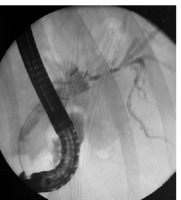

Figure 5

Cholangiography 3 months after the initial procedure. Full patency of the metal stent is visible